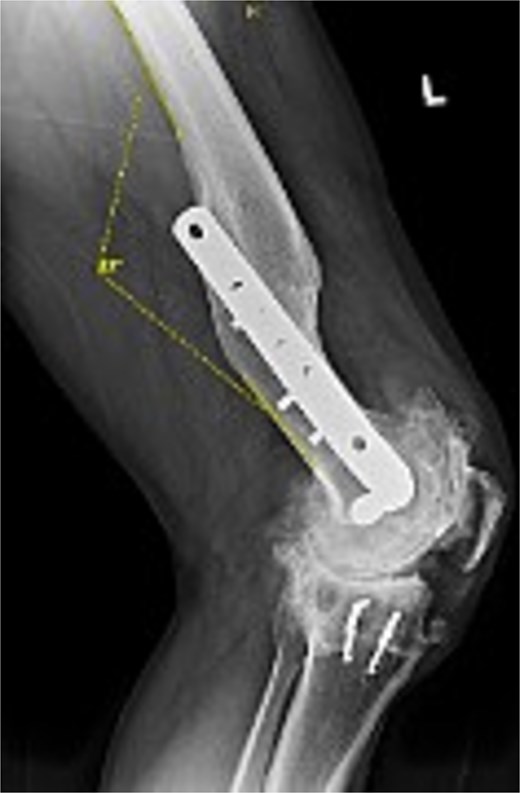

Preoperative radiographs revealed end-stage OA with osteophytes and subchondral sclerosis. Figure 1 shows the lateral view of the distal femur and knee. A healed malunion with significant recurvatum of 12° is evident, stabilized by a locking plate spanning the distal third of the femur. The plate and screws remained securely fixed, and the distal femur deformity altered the knee’s sagittal alignment with minimal impact on the coronal alignment. The AP standing long-leg radiograph (Fig. 2) demonstrated varus alignment of ~3°. The extra-articular deformity was located ~10 cm proximal to the knee joint line. No loosening of hardware or nonunion was noted. After discussing options, including staged deformity correction versus one-stage TKA, the decision was made to proceed with a single-stage TKA as the patient had a reasonable range of motion without hyperextension and a preference to avoid multiple surgeries.

Preoperative lateral radiograph of the left knee and distal femur. The pre-existing lateral plate and screws are seen along the anterior femoral cortex. A pronounced recurvatum malunion of the distal femur is evident measured at 12°. The knee joint shows severe tricompartmental osteoarthritic changes with joint space obliteration and osteophyte formation.